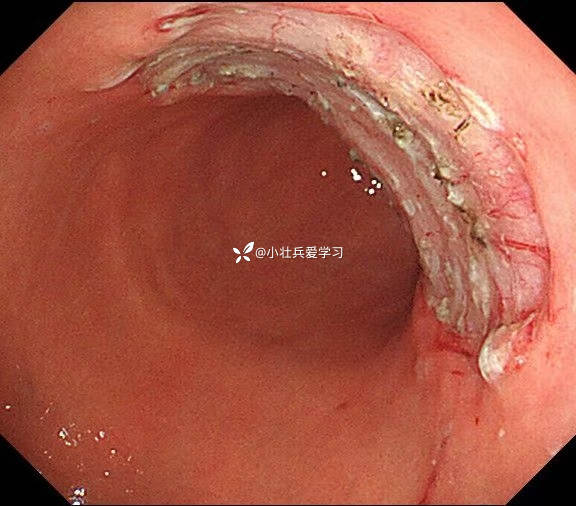

临床诊断:溃疡型胃角早癌

术前谈话诊断性ESD

术后病理示粘膜内癌(M3期),切缘阴性,达到治愈性切除标准,术后不用再追加外科手术、放化疗,对病人来说是不幸中的万幸。